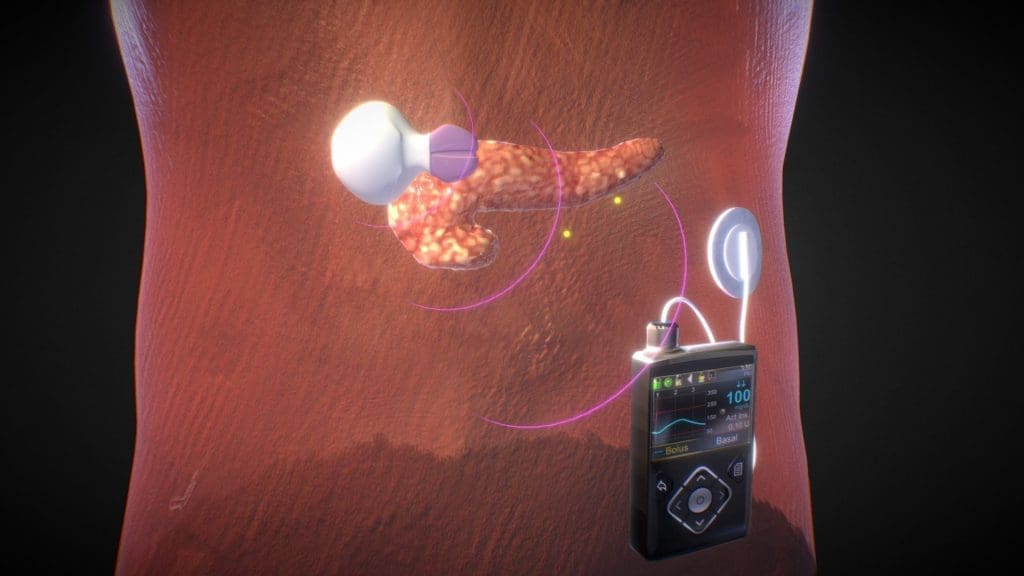

نغطي كل التخصصات الطبية

ان شبكة الاطباء والمشافي، تمكننا من اختيار افضل علاج باقل كلفة ممكنة

استیعاب کافة الحالات الطبیة لشمولیة التخصصات